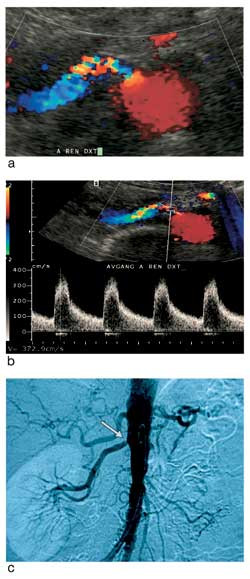

Med pasienten i ryggleie ble så aorta og nyrearterier undersøkt (fig 1). Etter vinkelkorreksjon ble det hentet ut dopplerkurver fra ulike avsnitt av arterien, særlig der det var påvist dopplerdistorsjon (aliasing). Hos alle overvektige har det vært forsøkt å fremstille nyrearteriene med gradert kompresjon og optimal innstilling for høy dopplersensitivitet. Målt maksimal systolisk hastighet (PSV) over 180 cm/s ble tolket som forenlig med signifikant stenose (fig 2). Det ble ikke brukt ultralydkontrastmiddel.

Sentral dopplerundersøkelse bygger på vurdering av blodstrømmen gjennom stenosen, med påvisning av økt hastighet. Systolisk maksimalhastighet (PSV) > 180 cm/s har i mange studier vist seg forenlig med en signifikant stenose i nyrearterien. Sammenliknet med angiografi er det funnet sensitivitet/spesifisitet på 92 % (8).